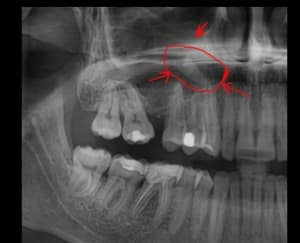

Если дискомфорт ощущается под коронкой живого или мёртвого моляра, важно провести рентгенографию для определения источника боли. В случае живого зуба причиной может быть кариес или воспаление корня и десны. Если же зуб мёртвый (нерв удалён), возможны следующие причины:

- Неполная пломбировка корневых каналов, что приводит к образованию пустот и, как следствие, воспалению.

- Облом медицинского инструмента, оставшийся в корне, может вызывать болезненные ощущения при контакте с холодным или горячим воздухом и жидкостями; боль часто локализуется в десне под коронкой.

- Применение некачественного пломбировочного материала, который со временем может проседать, создавая пустоты внутри каналов. Эти пустоты способствуют возникновению воспаления, и через несколько лет после протезирования может начаться боль в десне под коронкой.

Если коронка подлежит снятию, то сначала распломбируют верхушку, лечат воспаление, очищают канал и вновь пломбируют его. Важно провести лечение корней и каналов с последующим контролем на рентгенограмме. Рентгеновский снимок делают после пломбирования, чтобы убедиться в отсутствии пустот, пор или остатков медицинских инструментов внутри десны.